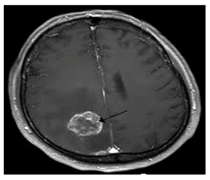

3.2. Separation of the Medical Image

The proposed method is based on the separation of the medical image into two regions: the anatomical region and the black background region. The separation can be done automatically by using an algorithm [4] or manually by using a rectangle to form the ROI [15,19]. In our method, we have used an automatic separation based on a threshold. The threshold was determined starting from the theoretical value 0 corresponding to the black pixel and iteratively increasing it by 1 until reaching a value making it possible to obtain a good separation between the anatomical region (ROI) and the black background region (RONI) for the images of the medical images database. A gray value greater than the threshold belongs to the anatomical object, and a gray value below or equal to the threshold belongs to the black background region of the image. Figure 2 shows an example of the anatomical region and the black background region separation.

Figure 2.

(a) the original image, (b) the anatomical region IAntomical, (c) the black background region IBlackbackground and (d) original image with separation between IAntomical and IBlackbackground.